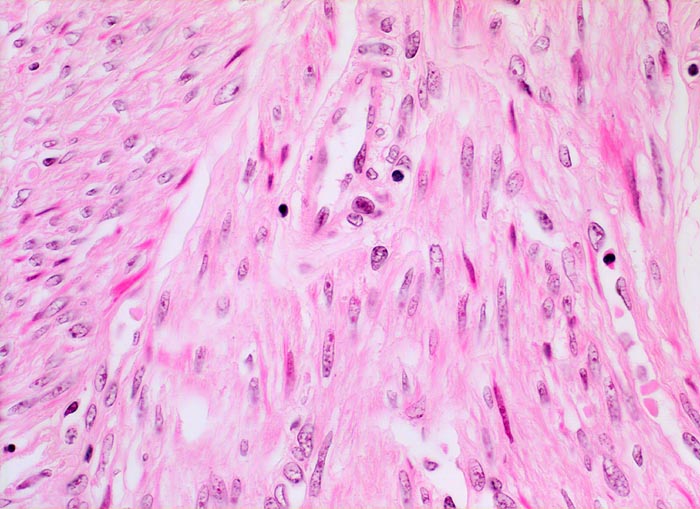

Fibroleiomyom des Uterus

benigner Tumor

Uterus

Die glattmuskulären Tumorzellen bilden geflechtartig verwobene Bündel. Zwischen den Tumorzellen verlaufen unterschiedlich breite zellarme Kollagenfaserzüge und dünnwandige Gefässe. Vereinzelte Entzündungszellen.

Vergrösserter 258g schwerer Uterus mit multiplen weissen, derben scharf begrenzten, teils intramuralen und teils submukös gelegenen Knoten.

Vaginale Hysterektomie wegen Meno-Metrorrhagien.

Histologie

400